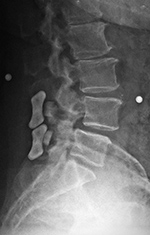

| 20 year-old woman with L1 vertebral body compression fracture treated with T12-L2 posterior spinal fusion using pedicle screws at T12 and L2 with connecting rods on each side. |